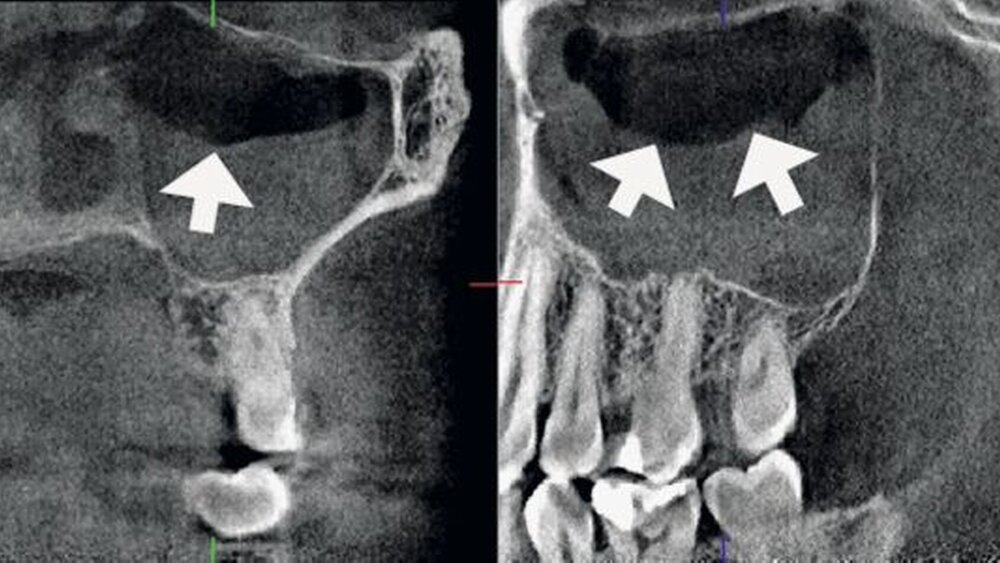

• Wurzelfrakturen [6] (wobei es jedoch Hinweise gibt, dass die Sensitivität für frische Wurzelfrakturen unmittelbar nach dem Trauma reduziert sein kann [50])• Alveolarfortsatzfrakturen [6]• intraossäre pathologische Veränderungen wie odontogene Tumoren [2] (Abbildung 1) oder größere periapikale knöcherne Läsionen [46]• Lageanomalien von Zähnen (Abbildung 2)• präoperative Schnittbilddiagnostik bei der geplanten operativen Entfernung von (teil-)retinierten Weisheitszähnen. Hier kann ein Einsatzgebiet für die DVT gegeben sein, wenn auf bereits vorhandenen, konventionellen Röntgenaufnahmen die räumliche Lagebeziehung zwischen Mandibularkanal und dem Weisheitszahn nicht ausreichend sicher interpretiert werden kann [11], oder als kritisch einzuschätzen ist [32]. Aufgrund des geringen Effektes bezogen auf den therapeutischen Nutzen sollte hingegen auf einen routinemäßigen Einsatz vor Weisheitszahnentfernung verzichtet werden [3].

• odontogene Tumoren [13] (Abbildung 1)• Knochenpathologie und -strukturanomalien insbesondere bei Ostitis, Osteomyelitis und Osteoporose• Kieferhöhlenerkrankungen (Abbildungen 3 und 4)• Speichelsteine• (knöcherne) Kiefergelenkerkrankungen• Kiefer- und Gesichtstraumatologie• Darstellung des räumlichen Verlaufs intraossärer Strukturen (knöcherne Nerven-, Gefäßkanäle)• Diagnostik und Operationsplanung bei komplexen Fehlbildungen (Abbildung 2)